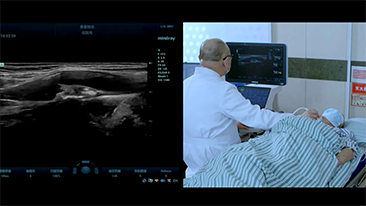

Solusi Pencitraan Umum Resona dari Mindray membantu para dokter mewujudkan diagnosis dan hasil pengobatan yang lebih akurat dan efisien melalui pemerik aplikasi subdivisi yang komprehensif dan alat bantu aplikasi klinis yang efisien.

Lingkungan medis saat ini telah menjadi lebih kompleks, dengan peningkatan jumlah kasus yang sulit dan beban kerja.